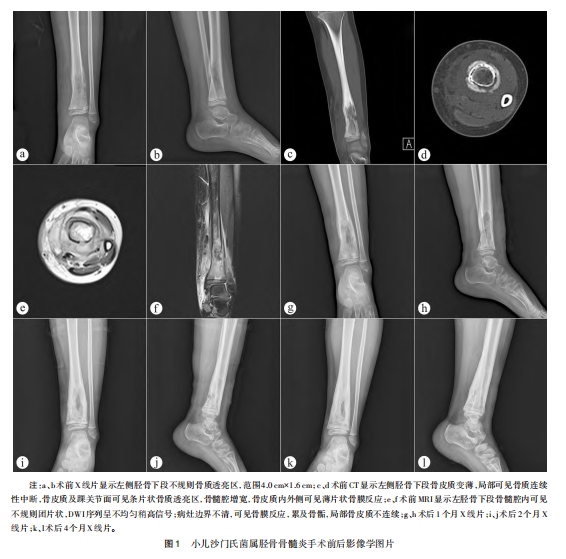

、C-反应蛋白、降钙素原正常。切口愈合良好,无发热不适,2024-10-14停静脉抗生素,出院后按药敏试验结果口服氨苄西林10周。术后1、2个月随访无发热症状,左下肢疼痛缓解,血常规、红细胞沉降率、C-反应蛋白正常;术后4个月X线片显示胫骨囊状骨质透亮区基本消失,邻近软组织无肿胀;术后6个月随访无不适,双下肢等长;术后8个月复查X线片未见异常,血常规、红细胞沉降率、C-反应蛋白正常(图1)。